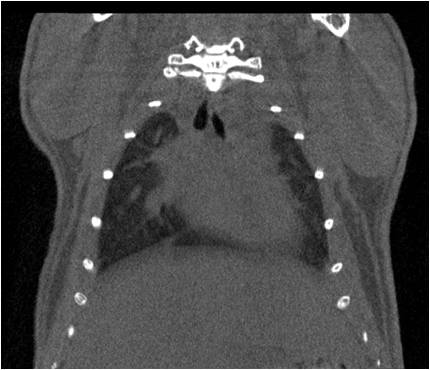

心血管

胸部和心血管的層析成像 胸部和心血管的3D圖像